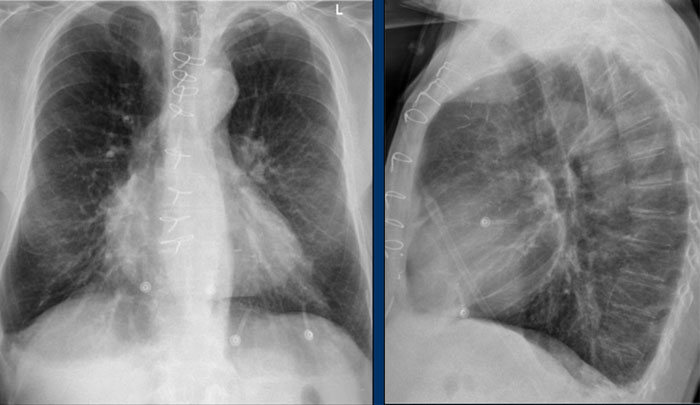

PA view

On the PA chest radiograph, careful evaluation of all interfaces between the lungs and adjacent structures—such as the diaphragm, heart, and mediastinum—is essential.

At these interfaces, lung–soft tissue boundaries form visible:

• Lines or stripes (e.g., the right paratracheal stripe)

• Silhouettes (e.g., the aortic knob or left ventricular contour)

These lines and silhouettes serve as anatomical landmarks and help localize pathology. When these contours are displaced or obscured with loss of the normal silhouette, the silhouette sign is present—a key diagnostic feature .

• The paraspinal line may be displaced by a paravertebral abscess, vertebral fracture with hemorrhage, or extravertebral extension of a neoplasm.

• Widening of the right paratracheal stripe (>2–3 mm) may indicate lymphadenopathy, pleural thickening, hemorrhage, fluid overload, or congestive heart failure.

• Displacement of the para-aortic line can be associated with aortic elongation, aneurysm, dissection, or rupture.

A key mediastinal–pulmonary interface to assess is the azygoesophageal recess (yellow arrow).

Azygo-esophageal recess

The azygoesophageal recess is located below the level of the azygos vein arch.

In this region, the medial aspect of the right lower lobe abuts the mediastinum between the heart anteriorly and the vertebral column posteriorly.

On its left, it is bordered by the esophagus.

Deviation of the azygoesophageal line may result from:

• Hiatal hernia

• Esophageal pathology

• Left atrial enlargement

• Subcarinal lymphadenopathy

• Bronchogenic cyst

On the PA chest radiograph, a lateral displacement of the azygoesophageal line can be seen.

It is caused by a hiatal hernia.

The arrow points to the barium contrast within the hiatal hernia.